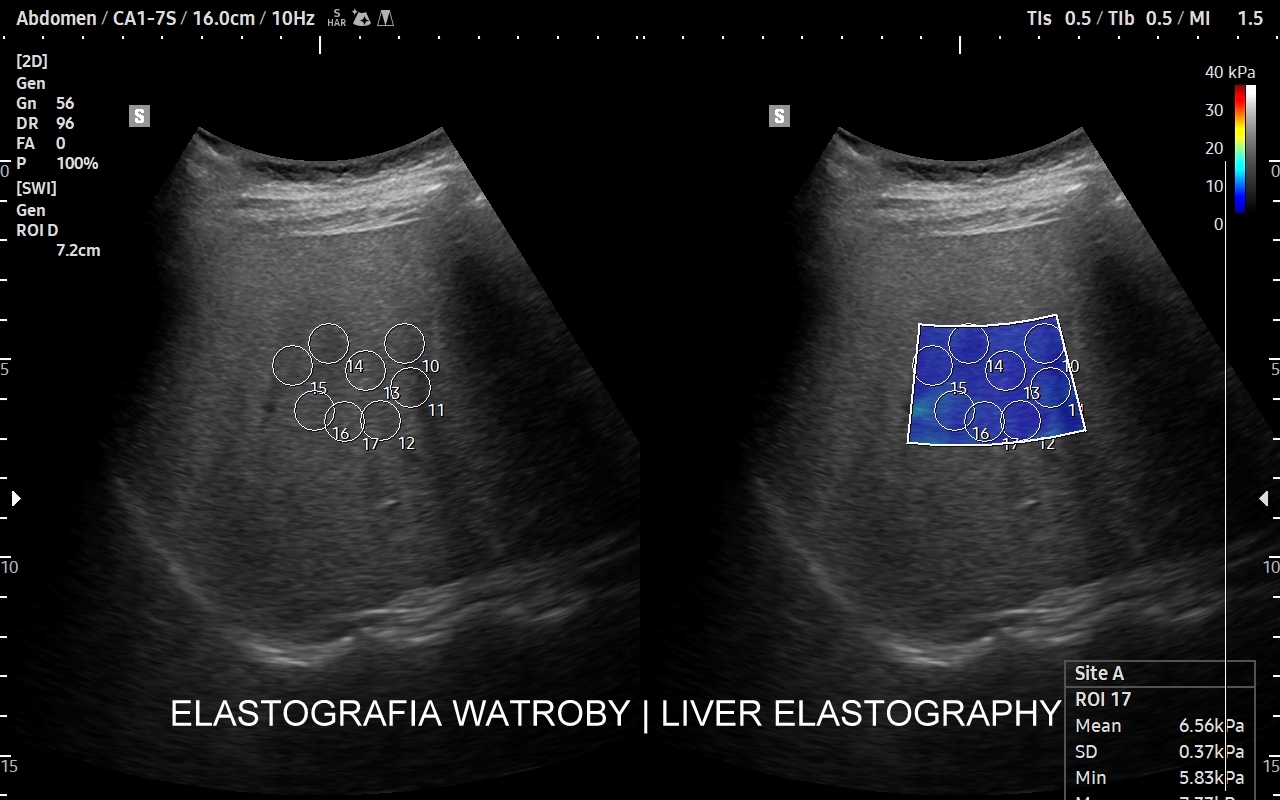

Na przestrzeni czasu metoda SWI ulegała ewolucji. Jej starsza odmiana to tzw. Fibroscan, który jest badaniem „na ślepo”, gdyż nie umożliwia precyzyjnego wyboru miejsca oceny miąższu wątroby. Odmianą najnowszą i wysoce precyzyjną jest elastografia 2D-SWE (2D sheer wave elastography). W badaniu 2D-SWE możliwy jest wybór konkretnego miejsca pomiaru w obrębie wątroby; dodatkowo generowana jest mapa kodowaną kolorem odpowiadająca mnogim punktom pomiaru, które następnie w trakcie post-processingu można wybrać w celu uzyskania dokładnego i wiarygodnego wyniku.

W jakim celu wykonywana jest elastografia wątroby? Elastografia 2D-SWE precyzyjnie ocenia sztywność miąższu wątroby, która to wzrasta w procesie włóknienia na tle przewlekłych schorzeń narządu, np. zapaleń. Badanie pozwala w ten sposób ocenić stopień zaawansowania zwłóknienia lub marskości wątroby. Dokładność oszacowania zwłóknienia w elastografii 2D-swe jest na tyle precyzyjna, iż zastępuje ona w omawianym wskazaniu medycznym biopsję wątroby.